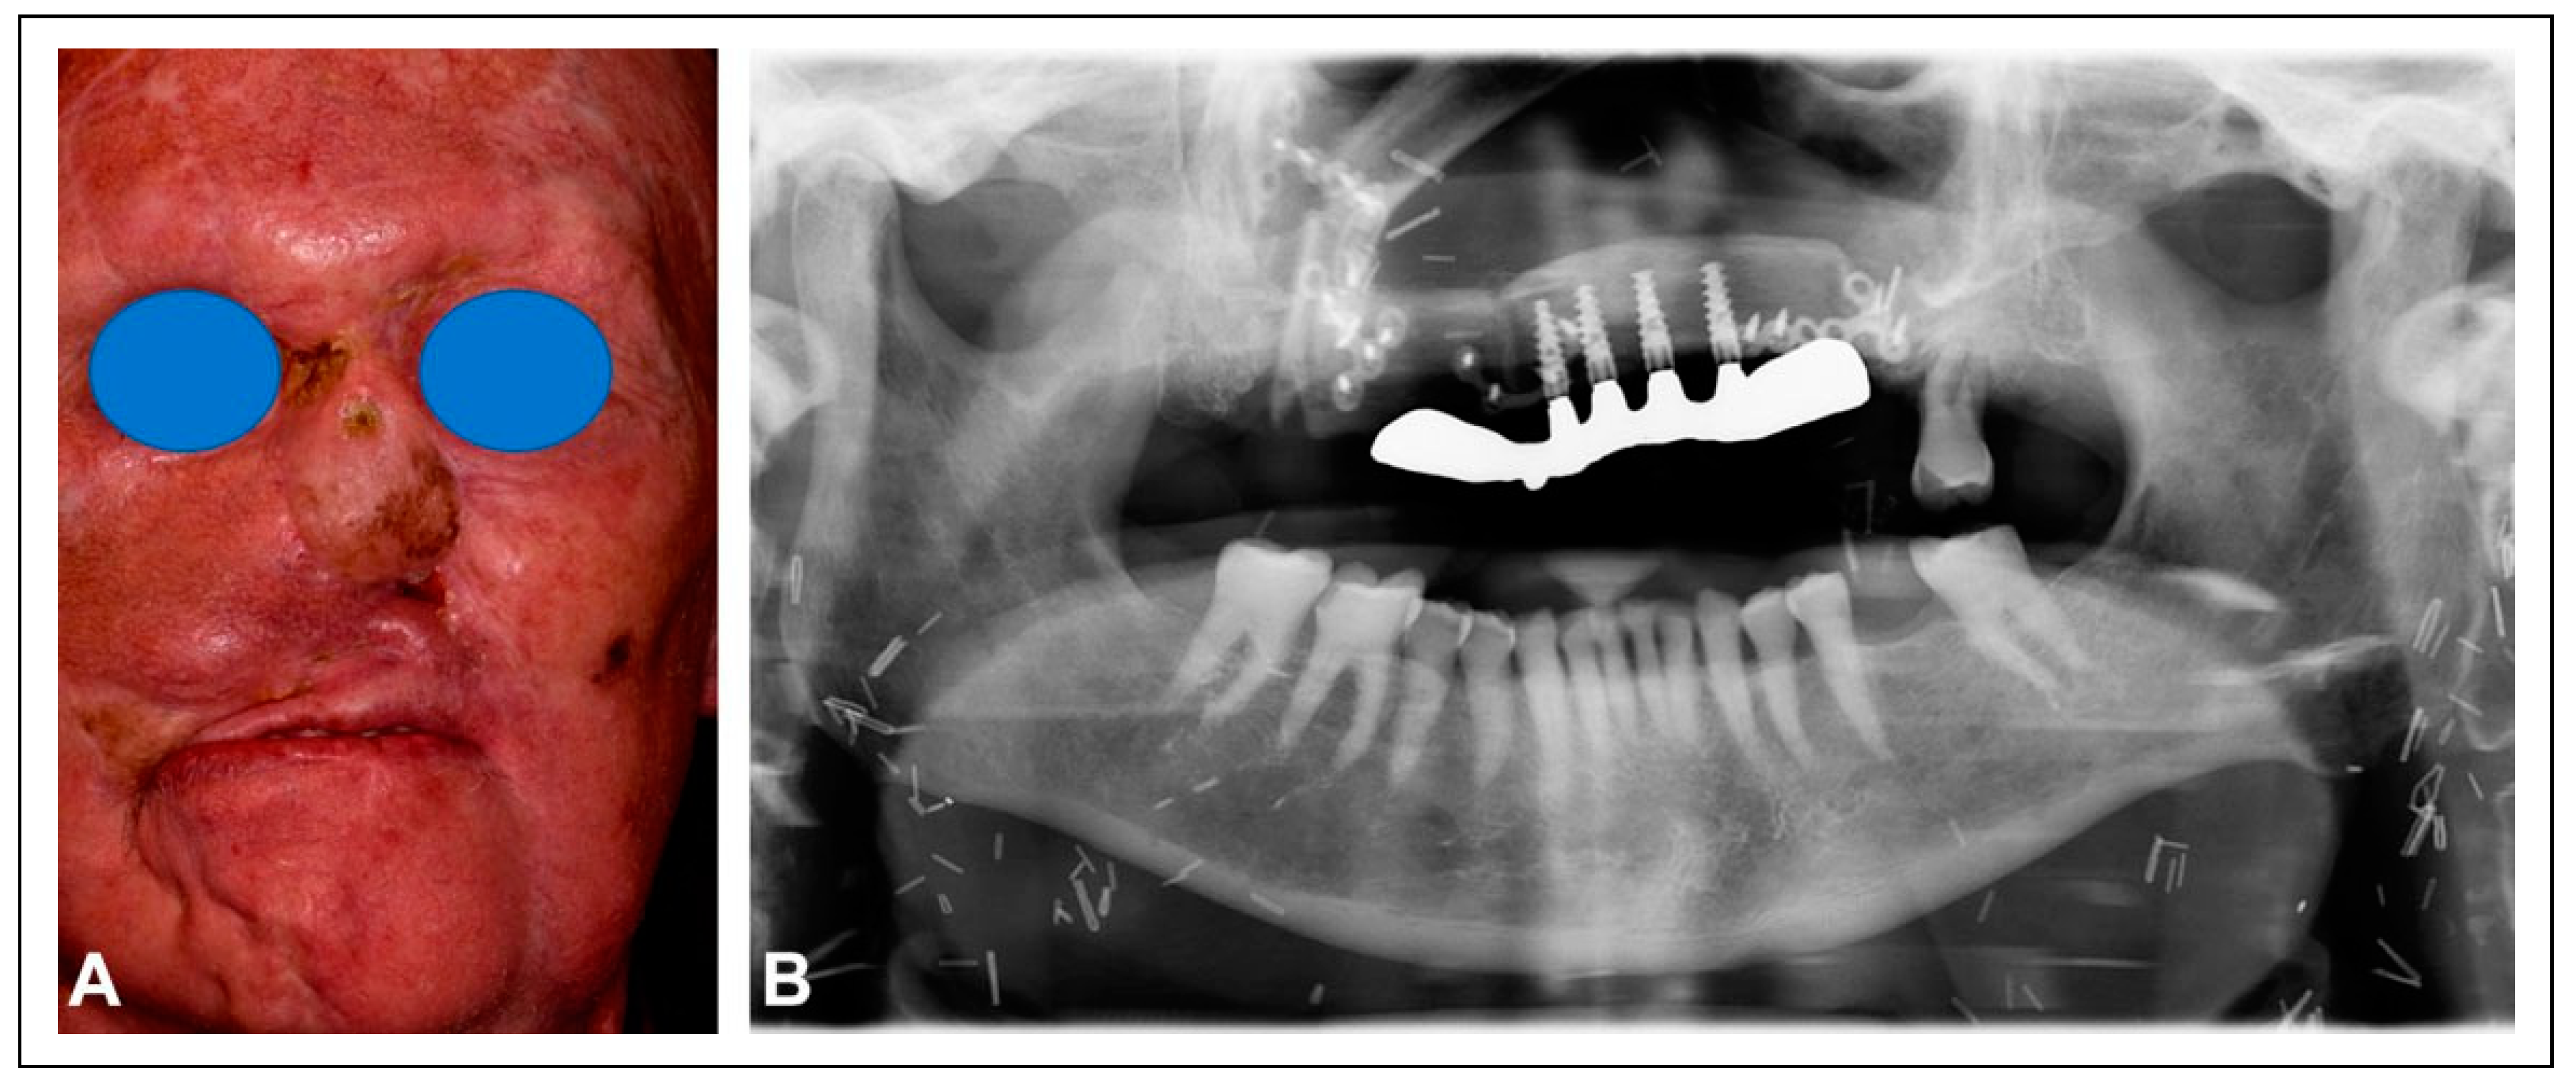

Figure 2. Having completed the first stage in the reconstruction with a combined submental flap (A) and a radial forearm flap to resurface the palate, computer planning was performed. The 3D images demonstrate the extent of the midface defect (B) and the design of the fibular free flap to restore the palatal arch and to bring vascularized bone to the cephalad portion of the rhinectomy defect for placement of implants to support a nasal prosthesis (C). The complexity of the bone design and contouring is demonstrated (D).

The second stage was performed three months later with reconstruction of the palatomaxillary defect using a left fibular free flap. Preoperative computer planning was performed to achieve two goals: restoration of the palatal arch with vascularized bone (Figure 2); and the positioning of vascularized bone at the nasion to permit strategic placement of osseointegrated implants to support a nasal prosthesis (Figure 3).